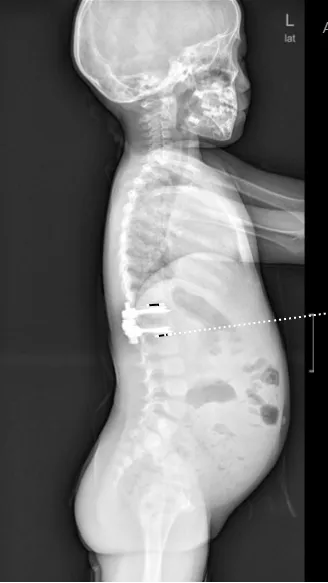

▷先天性脊柱畸形

先天性脊柱畸形,是指脊椎胚胎发育过程中,脊柱形成障碍或分节障碍所致的先天性脊柱畸形,包括侧凸、后凸和前凸,通常在婴幼儿期被发现。其中,半椎体畸形,尤其是完全分节的额半椎体,导致的脊柱侧凸保守治疗效果较差,早期诊断和手术治疗可避免严重的继发畸形,减少融合固定节段,保留更多的脊柱活动度,提高患儿生活质量。

▲ 女,7岁,先天性脊柱侧弯半椎体畸形